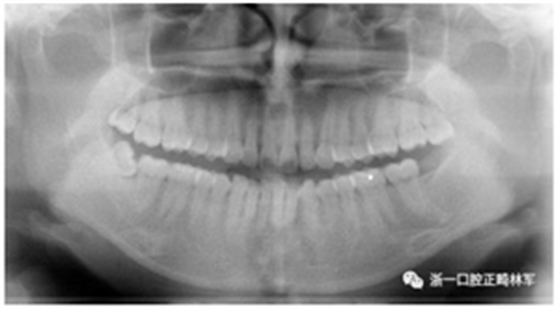

X線片檢查分析

初診全景片:牙齒數(shù)目形態(tài)未見異常,牙根未見異常。48近中阻生。